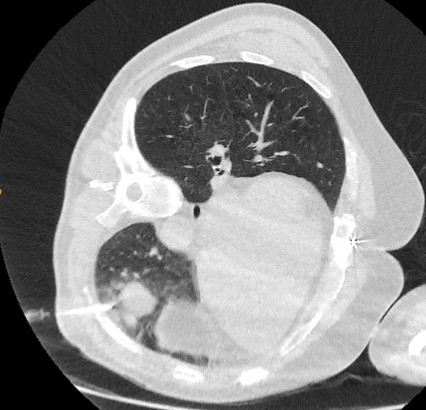

Solid nodules: volume doubling time of >600 days does not require follow-up, while a volume doubling time of <400 days, or clear growth defined as an increase in volume of 25% or more, suggests diagnostic investigations are required.[Figure caption and citation for the preceding image starts]: Computed tomography (CT) showing a right upper lobe spiculated solitary nodule within emphysema, in a current smoker with previous asbestos exposure. Note the visible pleural plaque on the left side. Resection histology revealed adenocarcinoma of the lungFrom the collection of Dr George Tsaknis, MD, PhD, FRCP(London), MRQA, MAcadMEd, PGCert; used with permission [Citation ends].